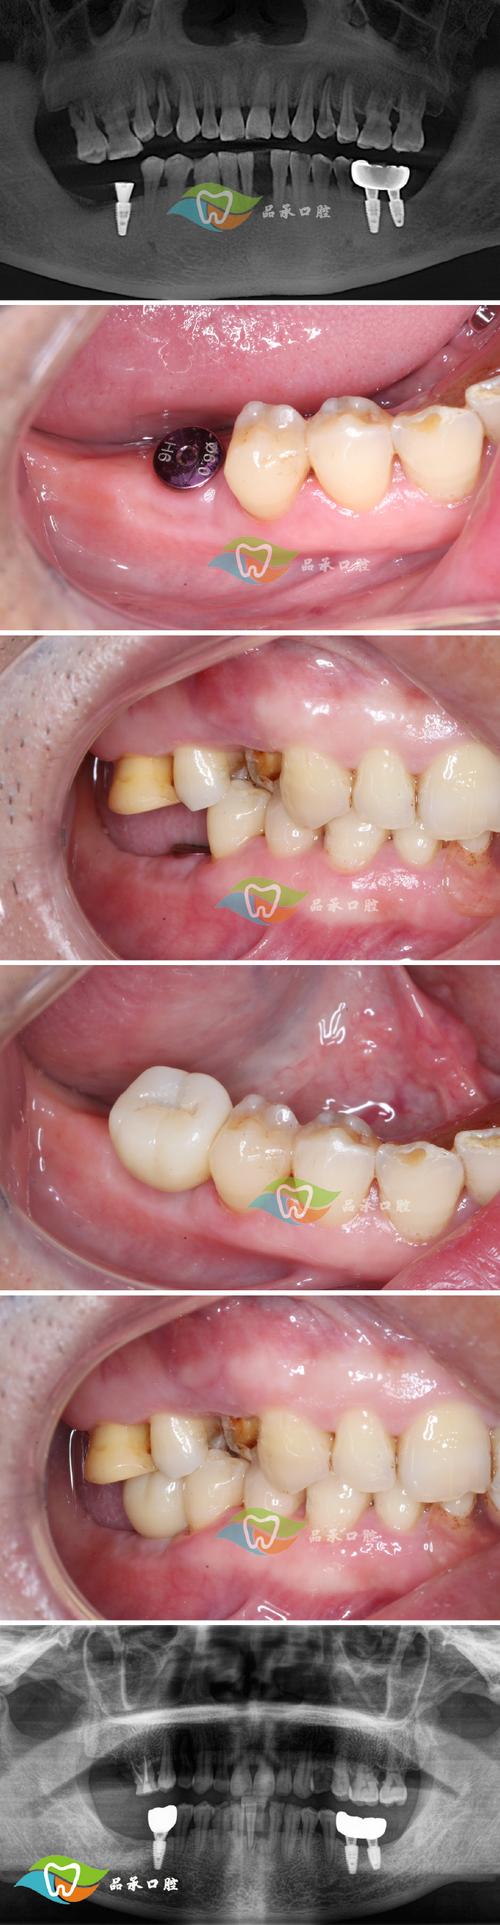

同福医植牙效果的核心理念是“精准与微创”,通过数字化技术与传统种植经验的深度融合,将手术误差控制在0.1mm以内,显著提升种植成功率与术后恢复速度,术前,采用CBCT三维影像设备获取患者牙槽骨的密度、高度及神经血管分布数据,结合3D口扫技术重建口腔模型,通过计算机模拟种植路径,确定种植体的最佳植入位置、角度及深度,避免损伤重要解剖结构,对于骨量不足的患者,还可借助数字化导板引导植骨或上颌窦提升术,确保种植体获得足够的骨支持。

术中,同福医采用动态导航技术,实时监控种植体的植入过程,确保其与术前设计方案完全吻合,相较于传统种植依赖医生经验的“盲种”方式,数字化种植将手术时间缩短至30-60分钟,术后肿胀、疼痛反应减轻60%以上,部分患者可实现当天种牙、当天戴冠,快速恢复基本咀嚼功能。

同福医植牙效果的最终体现,是让患者获得“以假乱真”的口腔修复体验,在功能层面,种植体通过基台与牙冠连接,形成独立支持结构,咀嚼效率可恢复至天然牙的90%以上,患者可正常进食坚果、排骨等硬物,无需担心脱落或损坏,美观层面,医生会根据患者的面部轮廓、肤色、邻牙形态及牙龈弧线,个性化设计牙冠的形态、大小及颜色,确保与邻牙色泽过渡自然,牙龈边缘无黑线,微笑时协调美观。

稳定性方面,成功的骨结合使种植体成为“天然牙根”,可承受垂直及侧向咬合力,不会像活动假牙一样基托压迫牙龈,避免黏膜萎缩及异味问题,临床数据显示,同福医种植的10年存留率达95%以上,部分患者使用15年以上仍功能良好,真正实现“一次种植,终身受益”。